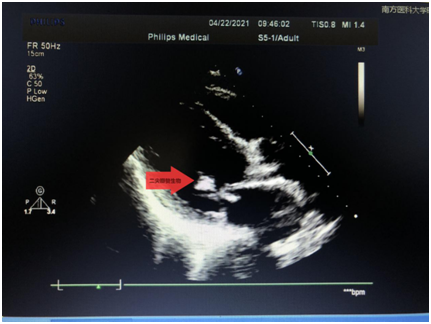

结果让杨大叔大吃一惊,原来他心脏里面的二尖瓣、主动脉瓣和三尖瓣都长了细菌,并因细菌的牵绊导致瓣膜关闭不全,从而造成血流反流。

更不幸的是,杨大叔心脏二尖瓣上面的赘生物大小已经超过1cm,属于极易脱落并导致脑卒中的高风险赘生物,需要尽早手术治疗。